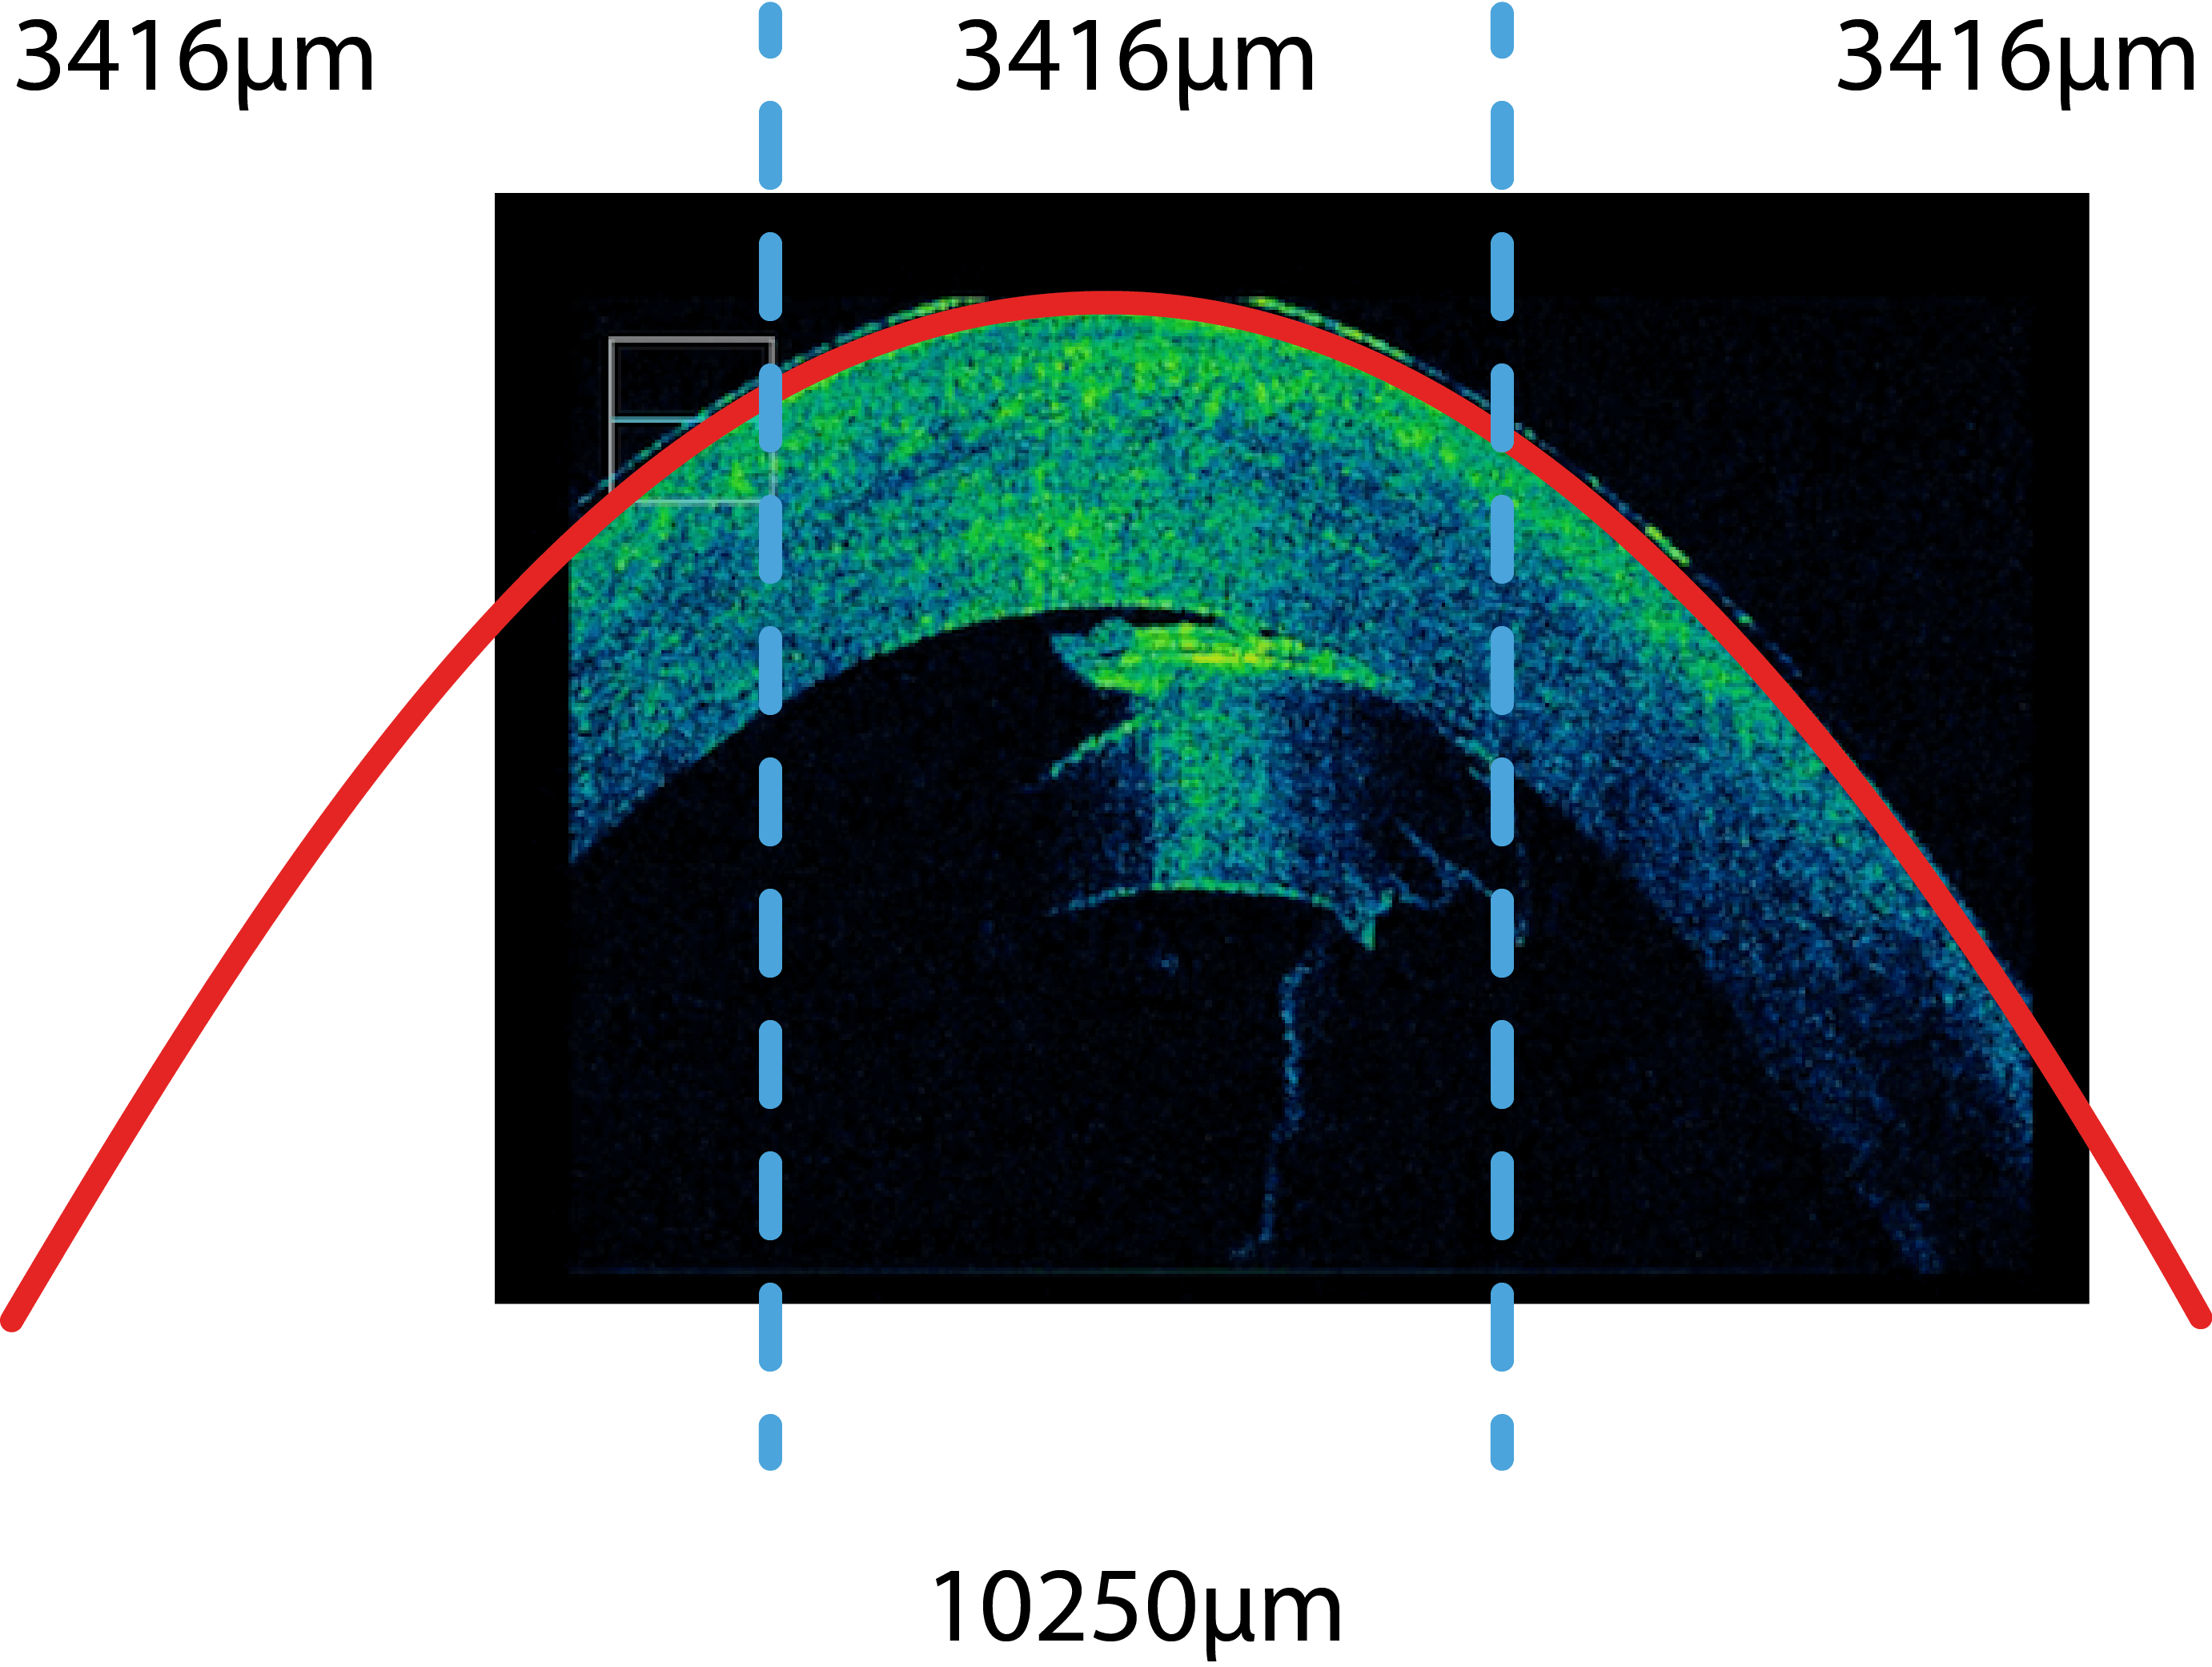

Prof. Findl verwendet zur Überprüfung des optimalen Sitzes des Transplantats ein hochauflösendes Schnittbildverfahren (OCT), welches in das Operationsmikroskop integriert ist. Prof. Findl war weltweit der erste Operateur, der mit dem Prototypen dieses Spezialmikroskops gearbeitet hat. Dadurch kann sichergestellt werden, dass keine Flüssigkeit zwischen Transplantat und Hornhaut vorhanden ist und es vermindert sich dadurch deutlich das Risiko einer frühen Transplantatablösung.

Schnittbildaufnahme während einer Katarakt-OP mit Linsenfragmenten die gegen das Endothel der Hornhaut drücken